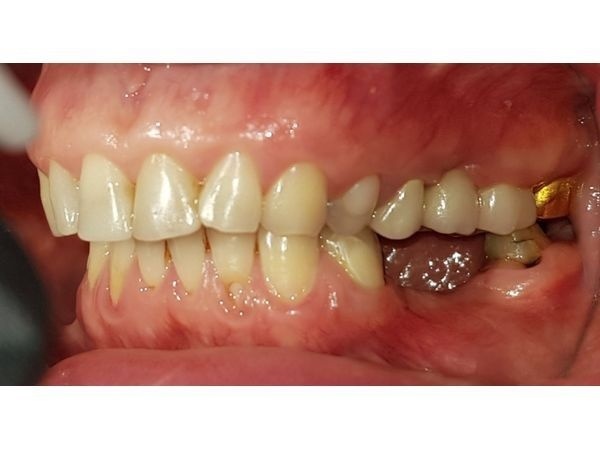

У пациентки не было некоторых жевательных зубов, на их месте стояли импланты и коронки, а дёсны вокруг отекли и кровоточили. Её также беспокоила стираемость зубов и сколы на старых пломбах.

Импланты и коронки на нижние моляры (зубы 35, 36, 45 и 46) установили около 2 лет назад в другой клинике. Примерно через год слизистая вокруг них воспалилась и отекла. Ещё спустя полгода женщина отметила разрушение жевательных зубов 37 и 47.

При осмотре определялось воспаление слизистой нижней челюсти вокруг коронок и имплантов. Старые пломбы прилегали неправильно и были сколоты. Зубы наклонены в сторону полости рта, при улыбке появлялись чёрные треугольники (вместо зубов виднелась пустота).

КТ показала очаги повреждения костной ткани вокруг имплантов, неточность прилегания коронок и большую зону разрушения кости в области 47-го зуба.